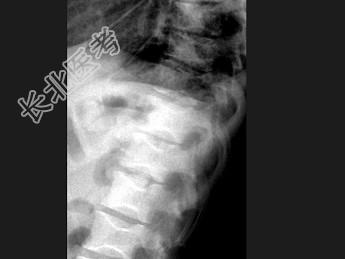

- 单项选择题女,28岁, 反复骨骼疼痛,结合图像, 最可能的诊断是 ( )

A、地中海贫血

B、镰状细胞贫血

C、白血病

D、脊椎退行性变

E、椎间盘突出